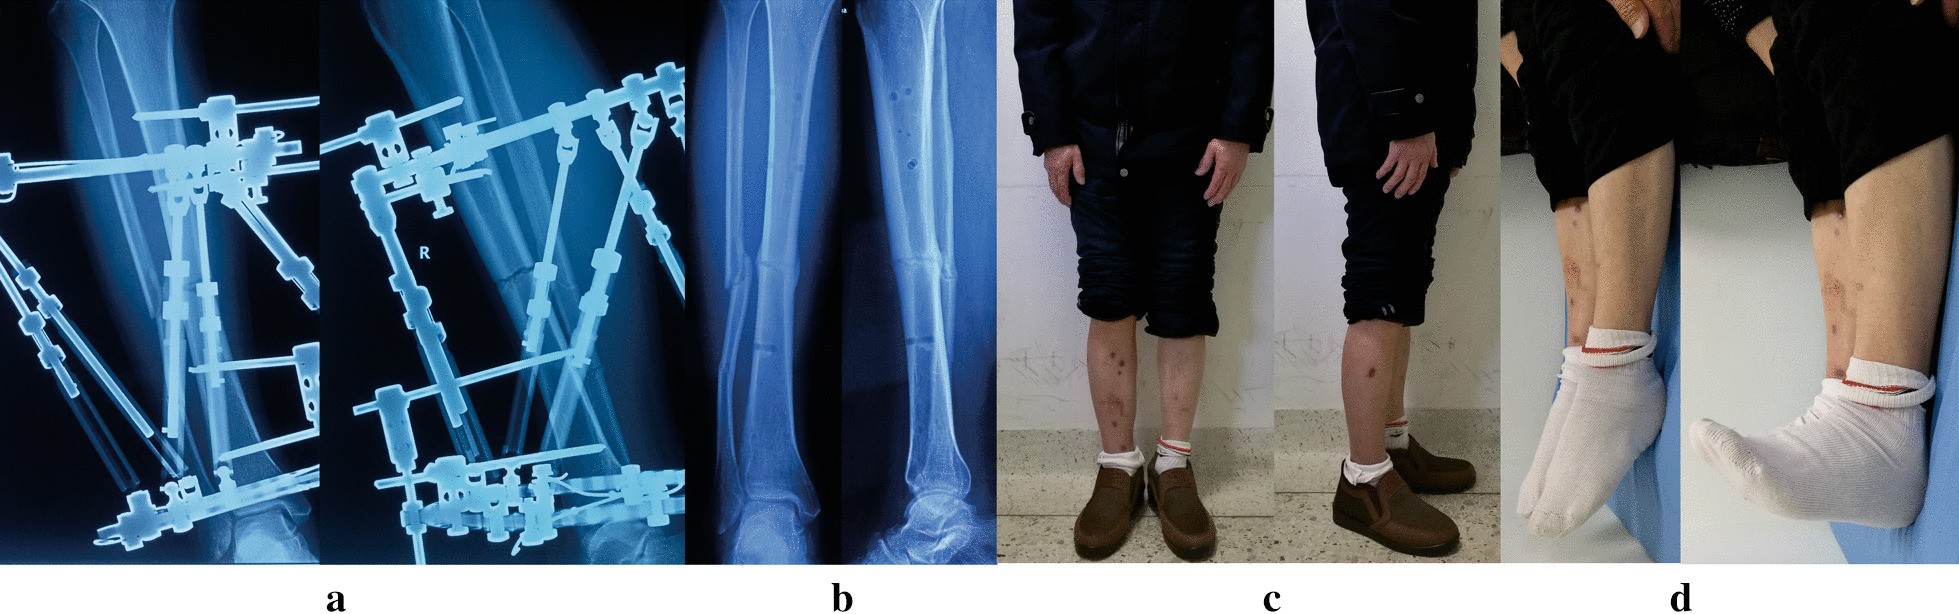

Fig. 2

From: Management of high-energy tibial shaft fractures using the hexapod circular external fixator

Images of the same patient shown in Fig. 1. a Radiographs after final correction. b Radiographs one months later after removal of TSF. c, d Clinical follow-up images, obtained at 12 months after TSF removal